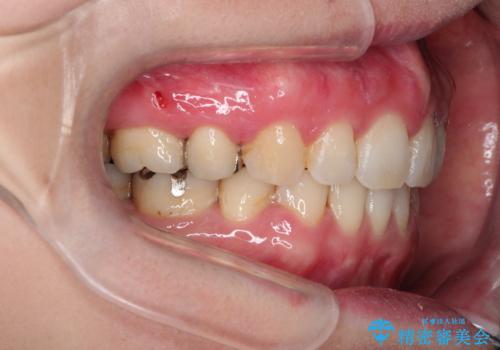

- 口が閉じずらく、口元が突出している状態でした。

上下左右の歯を1本ずつ、合計4本抜歯して、ワイヤーにて矯正することとなりました。

もともと下の前歯の永久歯が1本欠損しており、抜歯部位の選択を考慮しなければならない症例でした。シミュレーションを事前に行い、下顎の抜歯部位を決定しました。